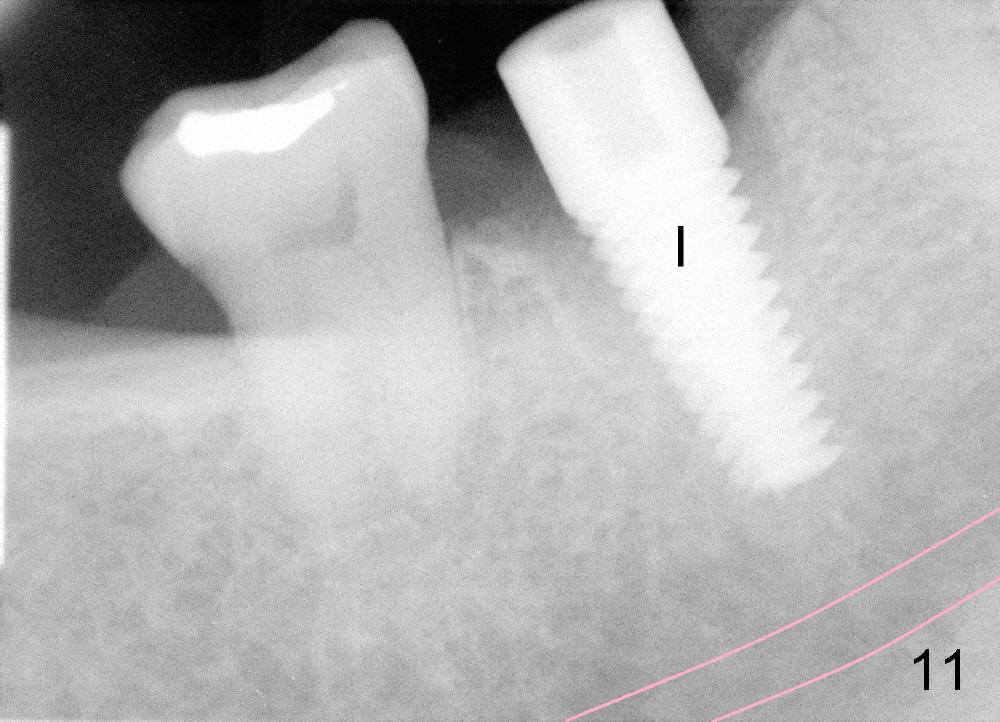

Septal bone is apparently pushed into the mesial and distal sockets (Fig.7 inset arrows) when a small round osteotomes is removed. The deeper portion of osteotomy is created by drills (Fig.8,9). The septal bone is further pushed mesiodistally as the osteotomy enlarges with combination of drills and osteotomes (Fig.10). A 6x17 mm tapered implant is placed with insertion torque >60 Ncm (Fig.11: I).